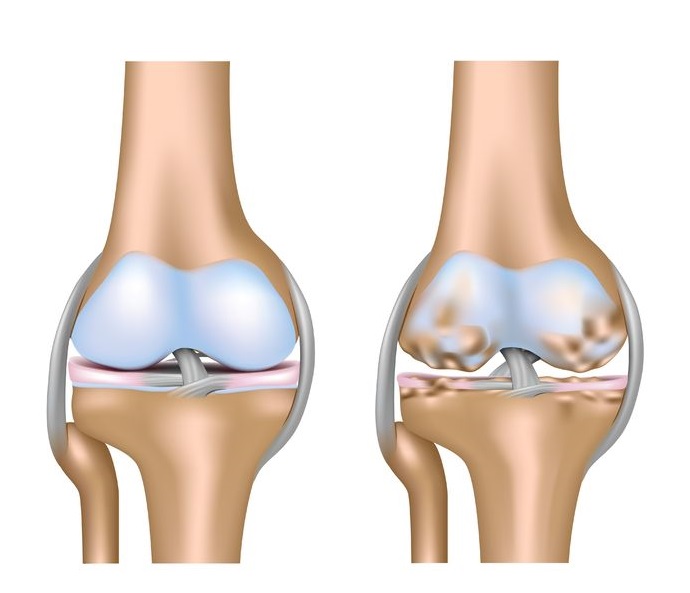

Diz Eklemi Osteartriti ( Kireçlenmesi )

Devamı